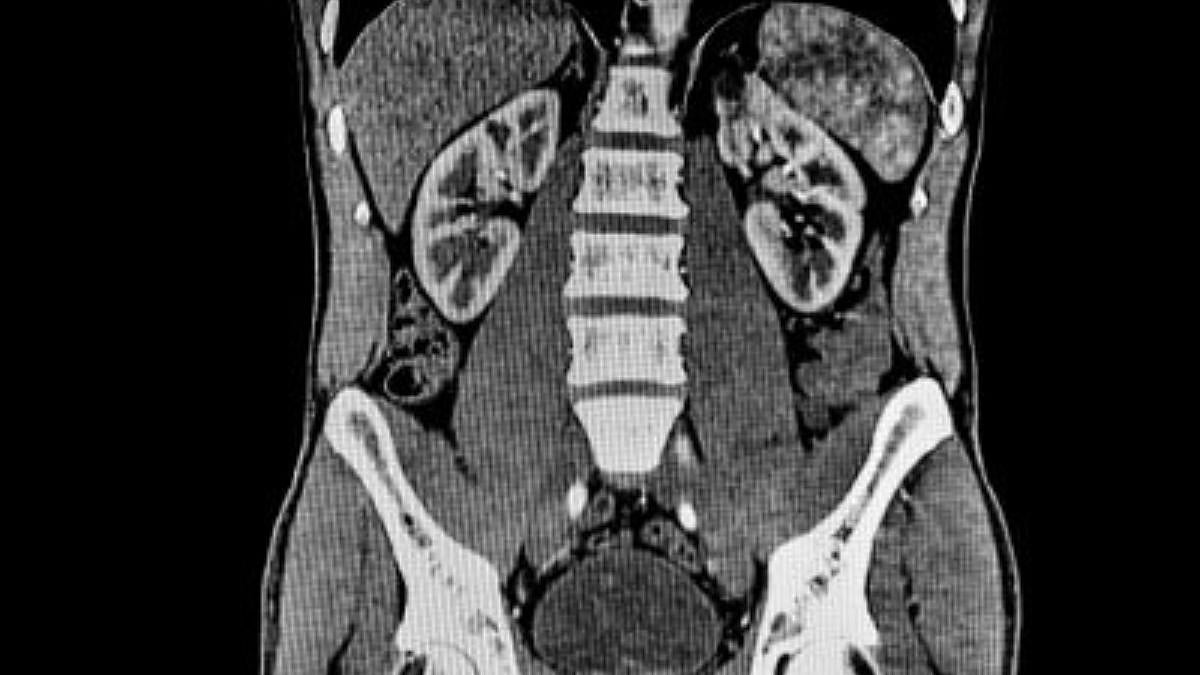

CT scan of the abdomen | National Institute of Biomedical Imaging and Bioengineering (NIBIB)